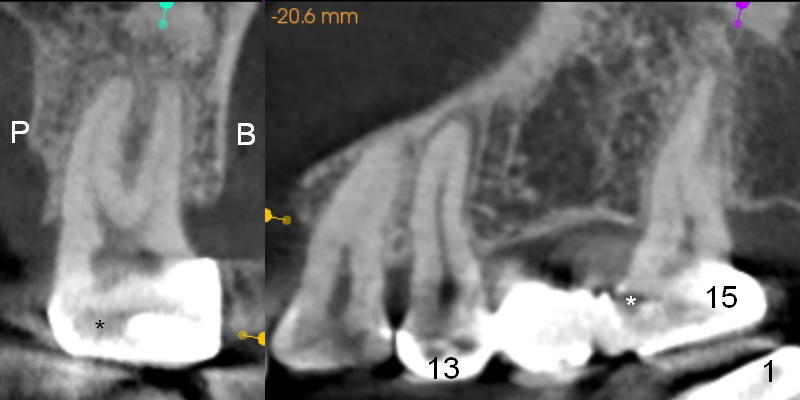

A 47-year-old woman complains of chewing pain at #15 after #30,31 implant placement. It appears that there is mesial open margin (caries, Fig.1). The bridge is to be sectioned at the junction between #13 and 14 (Fig.2 red line). It is expected that #14 and 15 units will fall out by themselves. Examine and remove caries at #15. Conduct pulpal test and start RCT if there is time and necessity. There is one common buccal orifice with two canals (Fig.2 arrowheads). Be prepared for provisional for #15. An implant will be placed at #14.